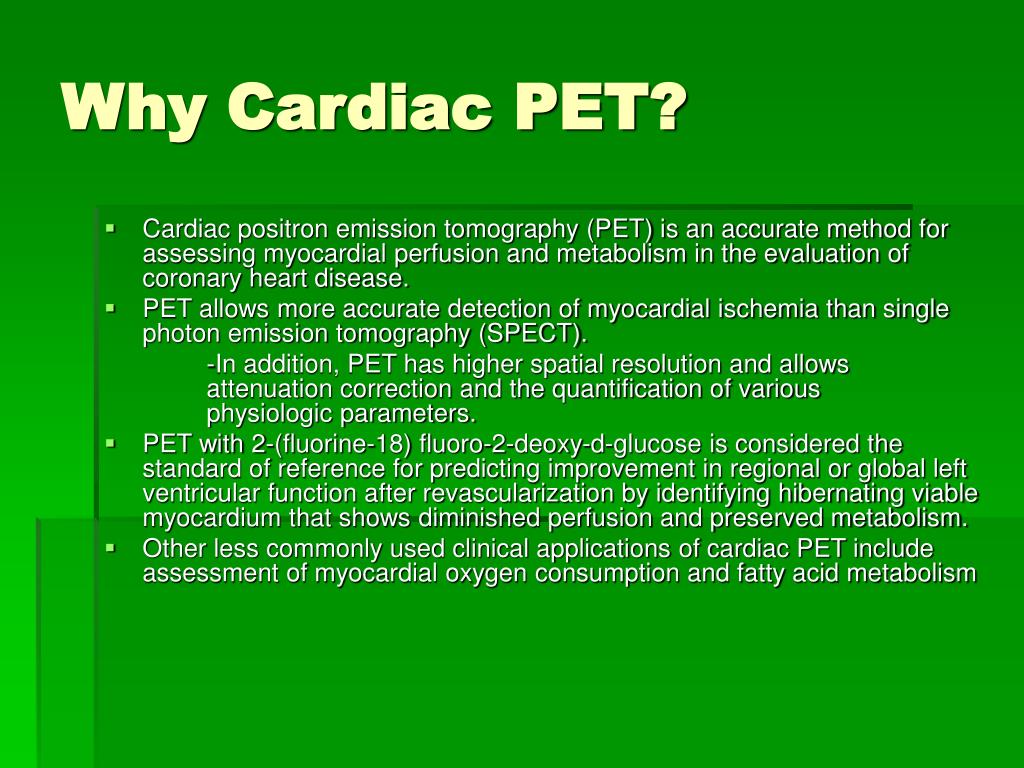

Enhance your business with our stunning commercial Cardiac Pet/ct collection of numerous professional images. optimized for commercial use with truck, vehicle, and automobile. ideal for corporate communications and branding. Discover high-resolution Cardiac Pet/ct images optimized for various applications. Suitable for various applications including web design, social media, personal projects, and digital content creation All Cardiac Pet/ct images are available in high resolution with professional-grade quality, optimized for both digital and print applications, and include comprehensive metadata for easy organization and usage. Discover the perfect Cardiac Pet/ct images to enhance your visual communication needs. Our Cardiac Pet/ct database continuously expands with fresh, relevant content from skilled photographers. Reliable customer support ensures smooth experience throughout the Cardiac Pet/ct selection process. Professional licensing options accommodate both commercial and educational usage requirements. Multiple resolution options ensure optimal performance across different platforms and applications. Regular updates keep the Cardiac Pet/ct collection current with contemporary trends and styles. Each image in our Cardiac Pet/ct gallery undergoes rigorous quality assessment before inclusion. Time-saving browsing features help users locate ideal Cardiac Pet/ct images quickly. The Cardiac Pet/ct archive serves professionals, educators, and creatives across diverse industries. Comprehensive tagging systems facilitate quick discovery of relevant Cardiac Pet/ct content.